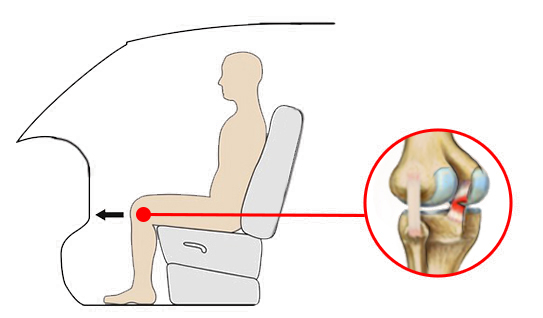

Uraz najczęściej występuje w wyniku wymuszonego tylnego przemieszczenia piszczeli. Do rozerwania PCL jest konieczna duża siła, dlatego bardzo często przyczyną urazu są wypadki samochodowe, gdzie dochodzi do uderzenia kolanem o deskę rozdzielczą.

Uraz najczęściej występuje w wyniku wymuszonego tylnego przemieszczenia piszczeli. Do rozerwania PCL jest konieczna duża siła, dlatego bardzo często przyczyną urazu są wypadki samochodowe, gdzie dochodzi do uderzenia kolanem o deskę rozdzielczą.

Orteza kolana RAPTOR/2RA stabilizuje staw w płaszczyźnie strzałkowej i czołowej. Orteza RAPTOR/2RA posiada 4-punktowy system podparcia, który doskonale stabilizuje i odciąża staw kolanowy. W przypadku uszkodzonego więzadła krzyżowego tylnego (PCL), kość piszczelowa ma tendencję do nadmiernego przemieszczania się w kierunku tylnym względem kości udowej. Konstrukcja przednio-tylna ortezy pozwala na zabezpieczenie piszczeli i ustawienie jej w osi stawu kolanowego.

W przypadku uszkodzonego więzadła krzyżowego tylnego (PCL), kość piszczelowa ma tendencję do nadmiernego przemieszczania się w kierunku tylnym względem kości udowej. Konstrukcja przednio-tylna ortezy pozwala na zabezpieczenie piszczeli i ustawienie jej w osi stawu kolanowego.